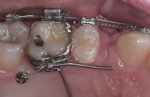

Besonders elegant ist dabei die Anbringung kleiner Pins neben den Zähnen oder im Bereich des Gaumens. Diese so genannten Mini-Implantate verankern sich zahnunabhängig im Kiefer und erlauben zielgerichtete Bewegungen. Die Behandlungszeit verkürzt sich entsprechend.